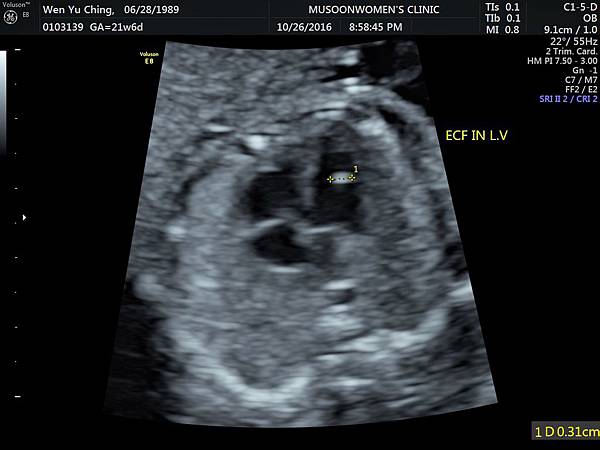

懷孕 (21-24W)高層次超音波: 左心室有一 顆小白點 嘖嘖